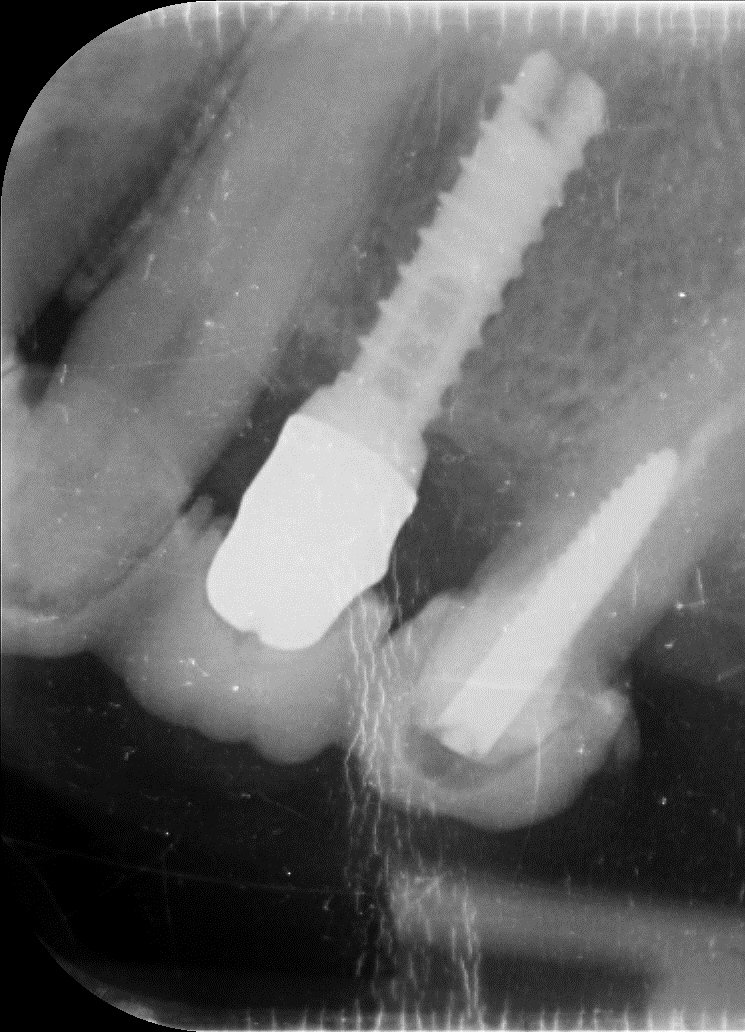

¿Podrían ayudarme a identificar el implante de la 36 ( mas mesial)?

Buenas tardes! Paciente que viene con corona floja, era cementada y um compañero intentando apretar el tornillo del pilar ( que se había aflojado) fresó la cabeza del tornillo. Necesito [...]